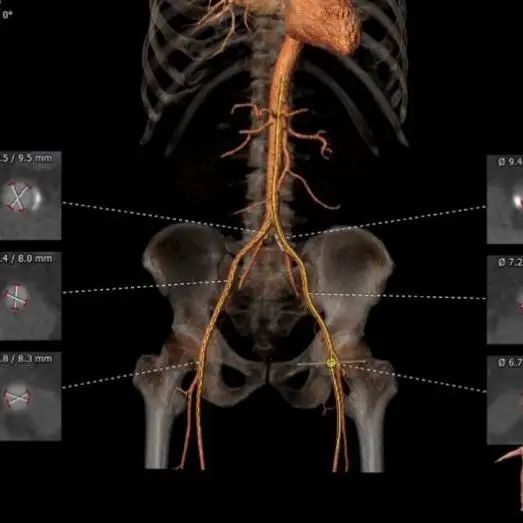

CT评估报告

瓣环平均直径:27.0 mm,左室流出道平均直径:26.8 mm。

升主动脉未见明显扩张,心脏角度:33°。

左冠高度:18.3 mm,右冠高度:17.1 mm。

左室明显增大。

优选右股入路,二尖瓣与主动脉瓣角度:127°。